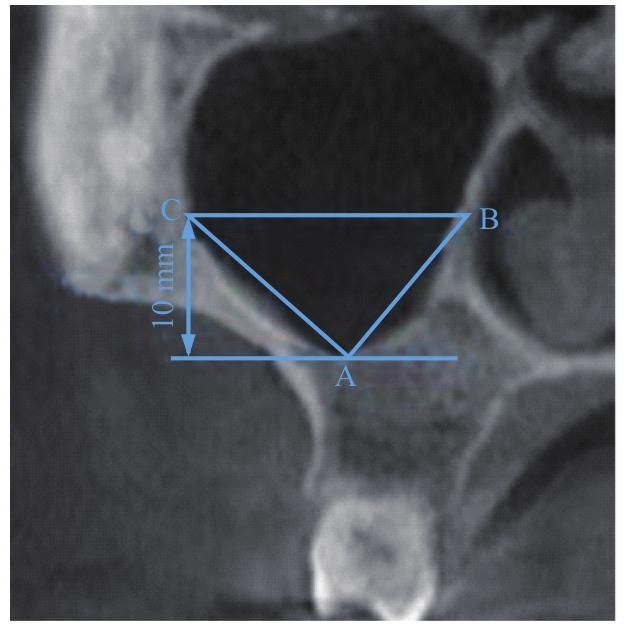

图2

M1牙位上颌窦角度测量方法

Note: Point A—The bottom of maxillary sinus in M1 tooth position; Point B—The intersection point of the parallel line and the medial wall of maxillary sinus; Point C—The intersection point of the parallel line and the lateral wall of maxillary sinus.

Fig 2

Measurement method of maxillary sinus angle in M1 tooth position